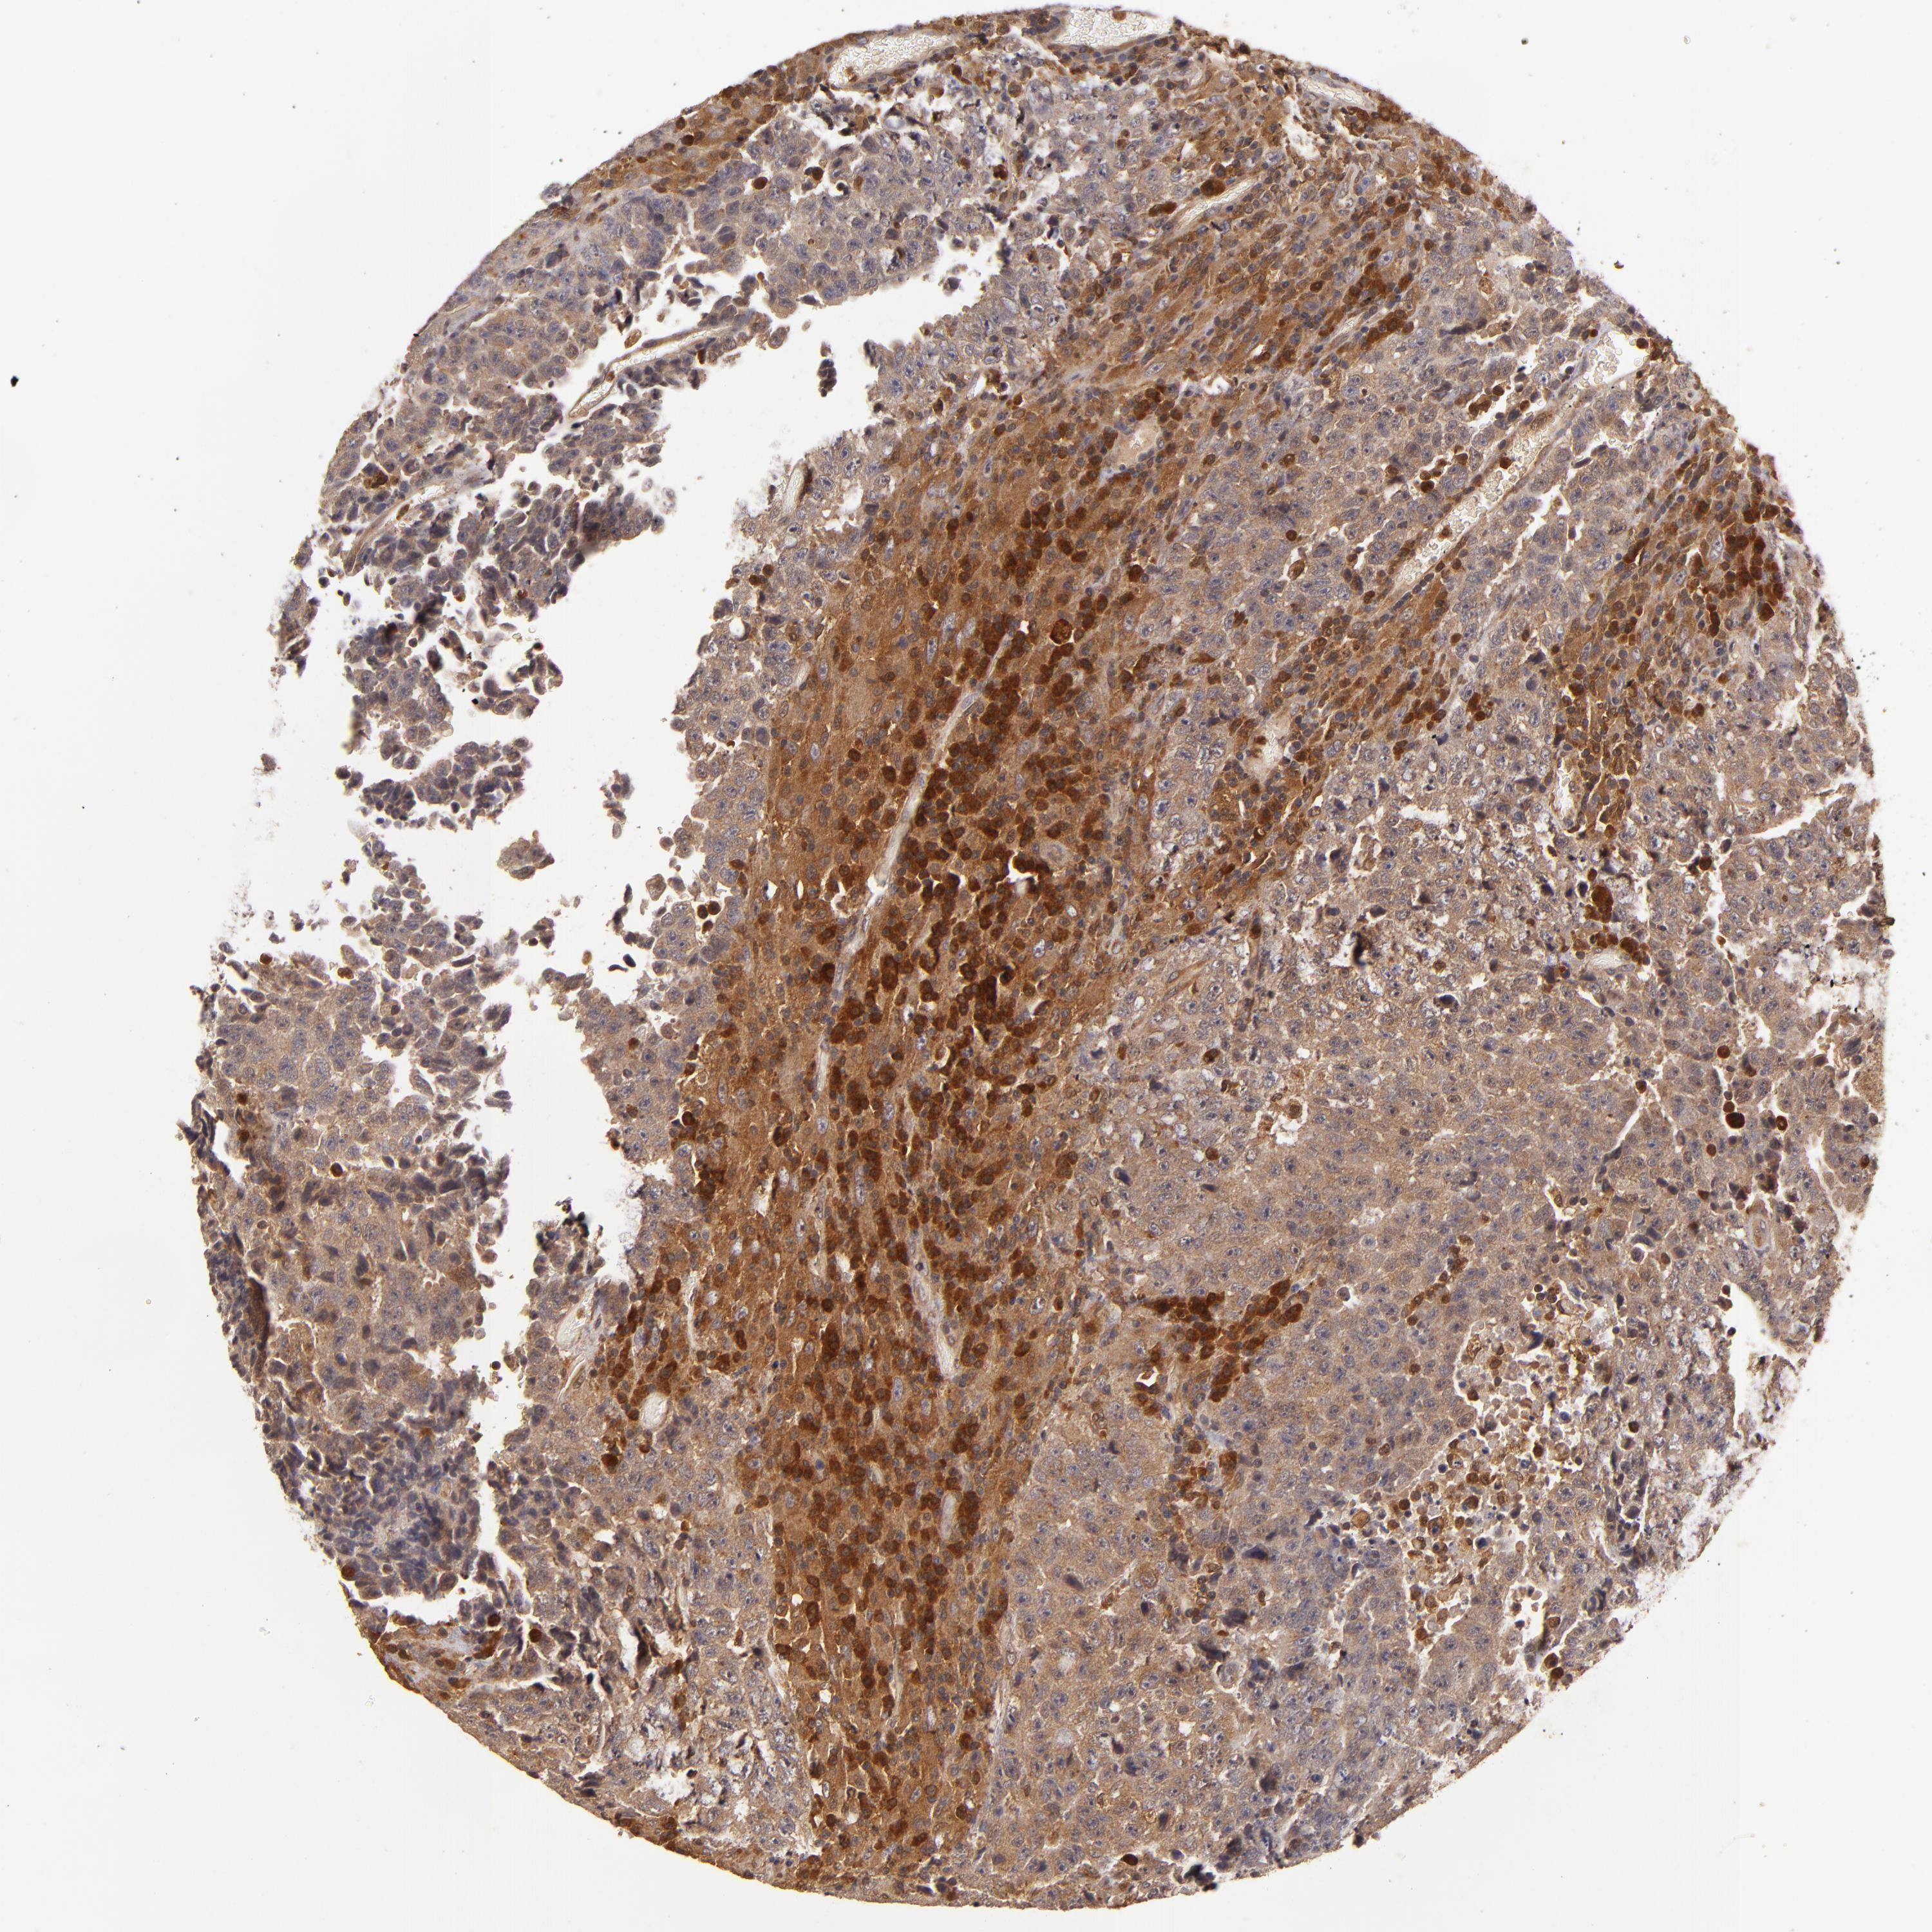

TESTIS CANCER - Protein expressioni

A mouse-over function shows sample information and annotation data. Click on an image to view it in a full screen mode. Samples can be filtered based on level of antibody staining by selecting one or several of the following categories: high, medium, low and not detected. The assay and annotation is described here.

Note that samples used for immunohistochemistry by the Human Protein Atlas do not correspond to samples in the TCGA dataset.

Antibody stainingi

Antibody staining in the annotated cell types in the current human tissue is reported as not detected, low, medium, or high, based on conventional immunohistochemistry profiling in selected tissues. This score is based on the combination of the staining intensity and fraction of stained cells.

Each image is clickable and will lead to virtual microscopy that enables deeper exploration of all samples and also displays staining intensity scores, fraction scores and subcellular localization as well as patient and tissue information for each sample.

Antibody HPA001863

High

Medium

Low

Not detected

Intensity

Strong

Moderate

Weak

Negative

Quantity

>75%

75%-25%

<25%

None

Location

Nuclear

Cytoplasmic/membranous

Cytoplasmic/membranous,nuclear

Carcinoma, Embryonal, NOS